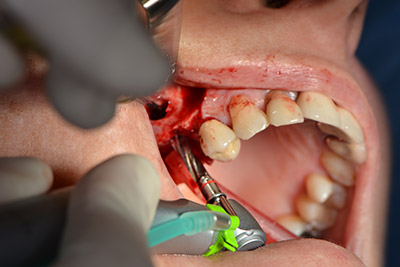

Procedura chirurgica per l'impianto

L'incisione classica (rilascio crestale e buccale) e la preparazione del lembo mucoperiosteo favoriscono un'ottima panoramica.

In questo caso vengono usati impianti di tipo SKY (bredent). Il loro protocollo chirurgico specifica una perforazione pilota di circa 1200 rpm (fig. 9).